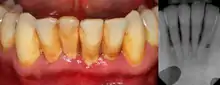

| Gingival enlargement can be a feature in some periodontal diseases. | |